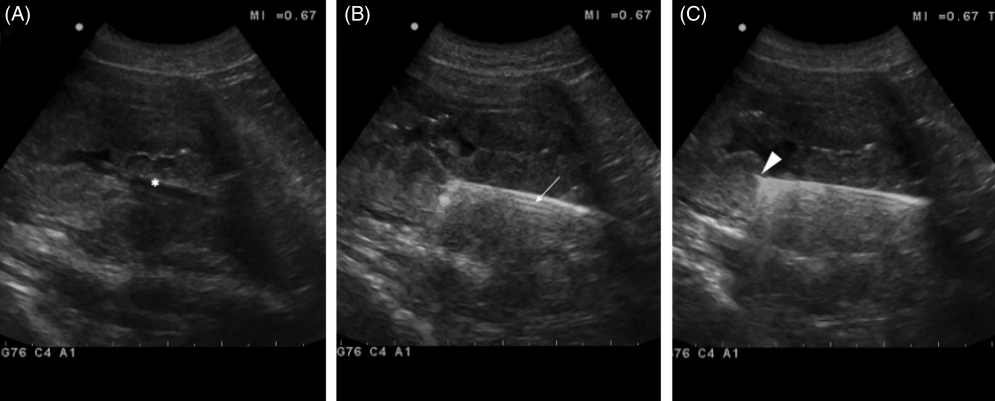

초음파와 내시경 포셉을 이용한 방광 조직생검 방법

내시경 검사를 할때 위장관 조직을 생검하던 바이옵시 포셉을 이용하여 방광내 TCC와 같은 종양을 조직 생검하는 방법에 대한 논문

당연히 샘플링 위치는 초음파 유도하에 한다.

시술 후 출혈도 초음파 검사중 도플러를 통해 대혈관을 피하면 어느정도 발생량을 줄일 수 있다고 하지만 생살을 뜯어내는데 피가 안나면 그게 더 이상한것.